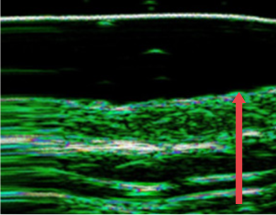

ก่อนฉีด

หลังฉีด

ปรับปรุงชั้นหนังแท้ของผิวหนังที่บางลงเนื่องจากความชรา การทำหัตถการผิวบ่อยๆ และการกระตุ้นจากภายนอก

หลังฉีด 4 เดือน

(ชั้นหนังแท้หนาขึ้น 12%)

หลังฉีด 7 เดือน

(ชั้นหนังแท้หนาขึ้น 27% )